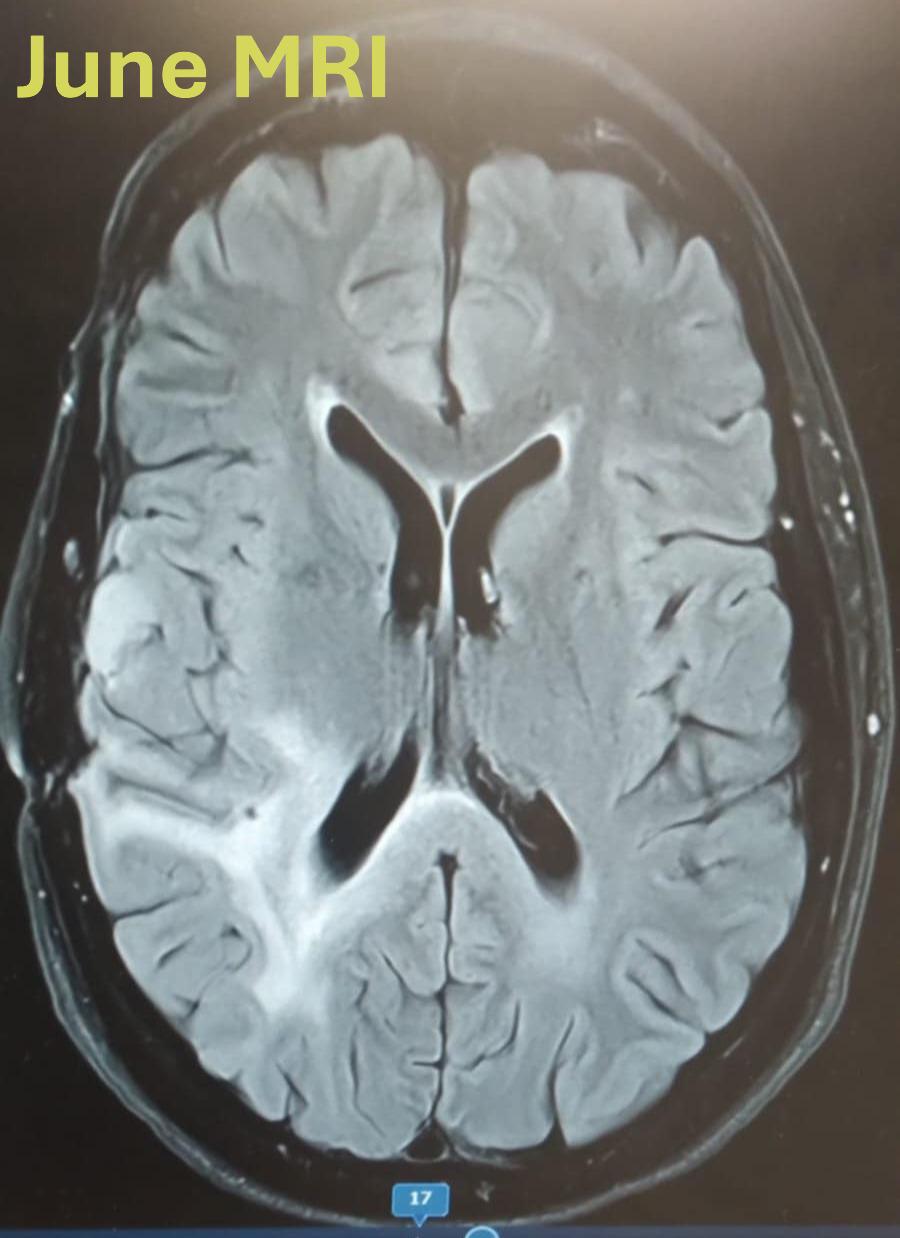

• "URGENT: MRI scans show a powerful story 💕

The latest MRI scans show a significant reduction in the temporal lobe tumor, and we're hopeful for a positive outcome.

June MRI shows the midline shift is back to normal! This is such a significant milestone in Danielles treatment and life style change. It just goes to show you, with true belief, maybe even stubborness on dani,s part 🙂, Proper treatment and support you can achieve anything!

The tumor has also reduced again and we are looking forward to seeing an even better result in the next MRI.